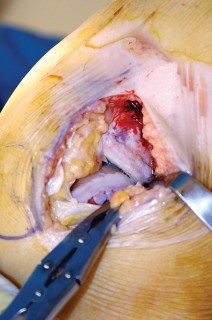

- تحرير الأنسجة الرخوة: يتم قطع الغضروف الهلالي لتحرير الأنسجة الرخوة من عظم الظنبوب، ويتم تطوير سديلة تحت السمحاق في نمط دائري حول الظنبوب. يُمدد هذا التحرير خلفيًا لضمان توازن الأربطة.

-

تصحيح التشوه:

الهدف هو تحقيق تصحيح طفيف للتشوه، مع وجود رخاوة كاذبة طفيفة عند تطبيق ضغط تفحجي في نهاية الإجراء. يجب تجنب التصحيح المفرط.